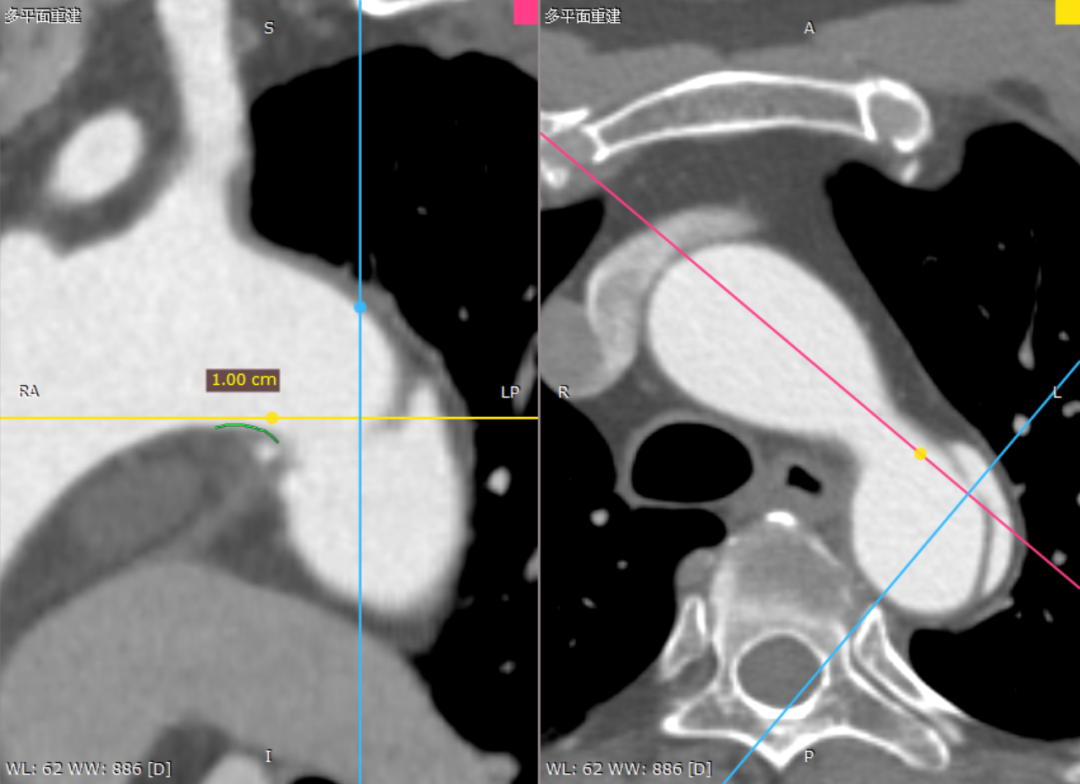

CTA详解:B型主动脉夹层,第一破口位于降主动脉前壁,距离LSA约10mm,LSA根部开口后缘处主动脉直径约29mm,Ⅲ型弓;病变范围广,远端与左肾动脉开口上缘齐平;双侧椎动脉等势,腹腔干、肠系膜上动脉、双侧肾动脉均由真腔供血。

术前三维重建

术前CTA横断面

近端锚定区10mm

Ⅲ型弓